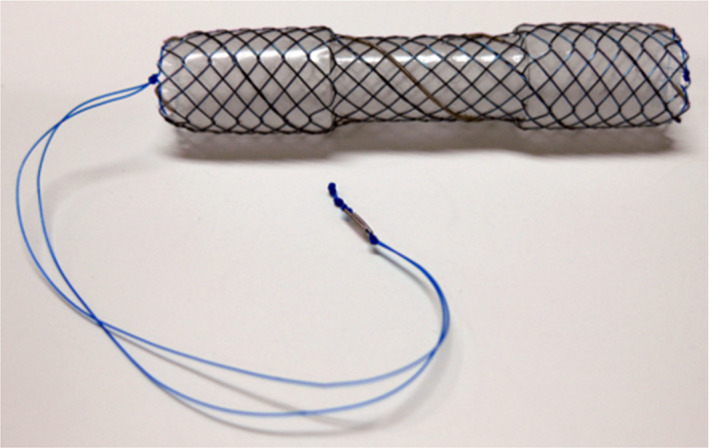

An endoscopic cholangiography revealed a stricture of the distal CBD and four CBD stones. The shortest diameter of each of the four stones (6, 5, 4, and 3 mm) was larger than the diameter of the distal CBD lumen (Figure 1B); therefore, endoscopic extraction of the stones was challenging. After endoscopic sphincterotomy (Figure 1C), we attempted to remove the CBD stones using a basket catheter, which is often used for the destruction of stones. However, the movement of the basket catheter was limited by the biliary stricture. Therefore, the basket catheter could only hold a small stone but could not extract them. The distal biliary duct was extremely narrow. Therefore, there was a possibility that the placement of multiple biliary plastic stents would be difficult, or they would not dilate the distal biliary stricture adequately to remove the CBD stones. Additionally, no pancreatic atrophy was observed during the imaging examinations. Due to the risk of injury to the pancreatic parenchyma, we did not perform dilatation with a balloon catheter. Considering all these factors, a CSEMS was placed to dilate the distal CBD stricture (Figure 1D–E). The CSEMS used in this case was BONASTENT M‐intraductal 8 mm 7 cm (Standard Sci Tech). The stent has a dumbbell shape, with an 8 mm diameter at both ends and a 6 mm diameter at the center (Figure 2). The distal tip of the stent was pushed out from the duodenum to prevent proximal migration of the stent. Due to the flared tips of the BONASTENT M‐intraductal, the risk of proximal migration of the stent is reduced. The diameter of the CSEMS (8 mm) was the same as the diameter of the CBD. The length of the distal biliary stricture was 3 cm. A 7 or 6 cm‐long stent had a midportion length of 2 cm, which is the longest BONASTENT M‐intraductal available commercially. In this case, the superior portion of the distal biliary stricture was slightly narrow. Therefore, we selected a longer stent of 7 cm. Before the CSEMS insertion, a 5‐Fr 12 cm straight pancreatic stent was placed in the main pancreatic duct to prevent postendoscopic retrograde cholangiopancreatography pancreatitis.11, 12, 13, 14, 15, 16, 17, 18, 19

A case report by Okabe et al9 described a case of CBD stones and distal CBD stricture due to CP. The CBD stones remained in the biliary duct and the upper portion of the CSEMS, and the distal biliary stricture did not improve despite CSEMS placement for 14 days. In contrast, the CBD stones spontaneously disappeared in our case, and the distal biliary stricture also improved slightly after the placement of the CSEMS for only 7 days. This indicates that the new CSEMS BONASTENT M‐intraductal (Standard Sci Tech) can lead to good dilatation. The stent’s dumbbell shape was thought to slightly prevent stent migration and transmit a dilation force to the CBD stricture.

However, complications such as migration and embedment have been reported when the CSEMS was left in place for a longer duration.10, 20, 23, 24, 25 A new dumbbell‐shaped CSEMS is thought to be useful in preventing migration. The duodenal tip of the dumbbell shape can prevent the embedment and migration into the biliary tract superiorly, while the hilar tip can prevent duodenal migration. If the new dumbbell‐shaped CSEMS migrates into the biliary tract superiorly, removal of the stent is thought to be easier than removing other types of the CSEMSs, primarily because the dumbbell‐shaped CSEMS becomes narrower by pulling a string that is attached at the duodenal tip (Figure 2). Park et al23 described that migration of the CSEMS is a risk factor that prevents the resolution of benign CBD strictures. The dumbbell shape is expected to prevent migration and dilate the CBD stricture effectively. In fact, in this case, the CBD stricture was slightly dilated after CSEMS placement for only 7 days.